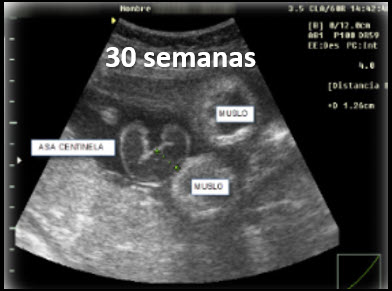

30 semanas de gestación

Puede observarse una mayor distensión intestinal. Estos hallazgos forman parte del seguimiento ecográfico seriado y deben interpretarse dentro del contexto completo del embarazo.